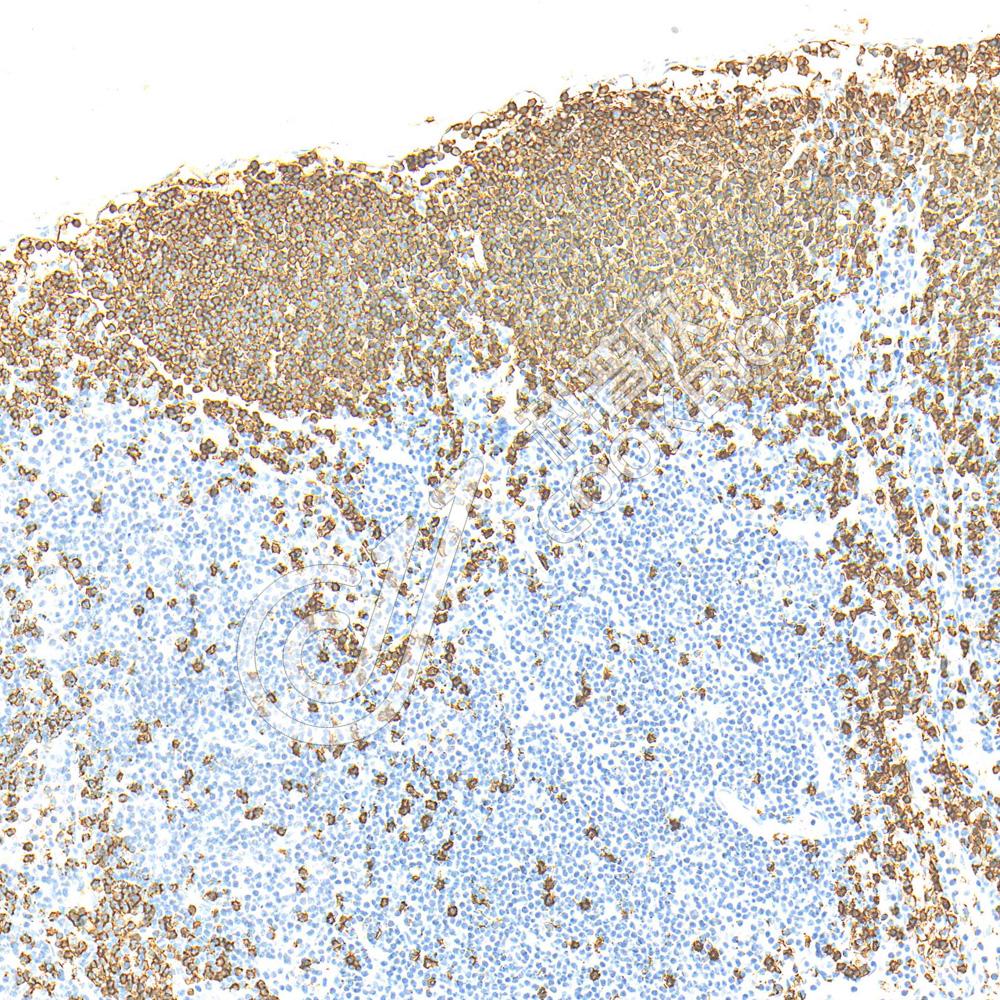

IHC检测CD3蛋白(货号 K1334011).

样品: 人扁桃体, 4%多聚甲醛 (货号KSG1101) 固定12-24小时.

抗原修复: 柠檬酸抗原修复液(干粉, pH 6.0) (KSG1201), 高压锅均匀喷气计时2分钟.

—抗: 1: 1100稀释, 4℃ 孵育过夜.

二抗: S-vision免疫组化多聚二抗(山羊抗兔),即用型 (货号KB3906), 室温孵育20分钟.